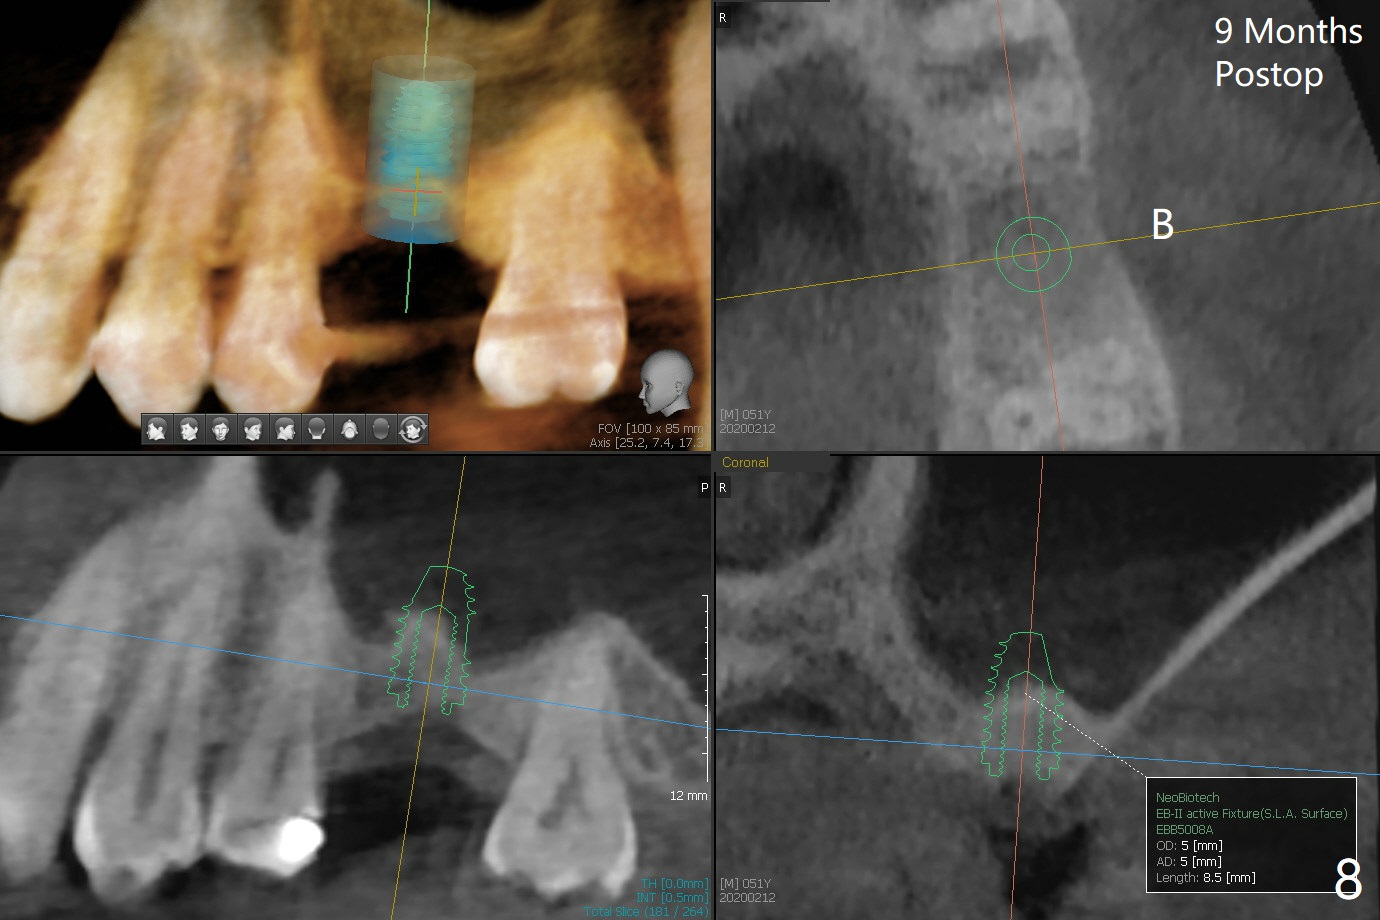

When the crown and abutment at #14 are removed, the implant is found to be shallowly placed. Upon incision, the implant threads are exposed circumferentially and coronal to the buccal crest (Fig.1 *). It seems to be difficult to expect bone regeneration post bone graft. The implant (6.4x6 mm) is removed with a 7/8 mm trephine bur, followed by sticky allograft (Fig.2 *), PRF membrane and 6-month membrane. In spite of the setback, the bone height increases from 3.9 mm to 11 mm due to sinus lift associated with the previous implant placement (Fig.2 L). The depth of the 2nd placement will be controlled by surgical guide. When the periodontal dressing dislodges 11 days postop, the 6-month membrane is lost as well as part of the bone graft. If there is remaining apical native bone, an immediate implant should be placed so that bone graft can be kept in place more securely with an immediate abutment and provisional! The seemingly conservative approach is actually not safe. The wound heals 1 month postop (following dislodgement of the 2nd periodontal dressing, Fig.3). Three months later, consider using bone expanders to do sinus lift and place a SM implant subcrestal. Take PA after 1st expander to the depth. The wound heals 4 months postop (Fig.4), but the bone height (Fig.5) and width (Fig.6) decreases. The latter continues to decrease 9 months postop (Fig.7,8), but bone density is high, average 1360 units. Preparation includes guide, incision, sinus lift, implant placement (possibly tissue-level (9) or FC if the sinus membrane perforates), bone graft, and suture.